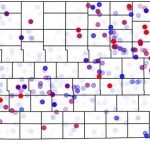

En el África subsahariana, 1 de cada 6 medicamentos contra el cáncer es defectuoso

Se encontraron graves defectos de calidad en un número significativo de medicamentos contra el cáncer procedentes del África subsahariana, según una nueva investigación de la Universidad de Notre Dame.

En el África subsahariana, 1 de cada 6 medicamentos contra el cáncer es defectuoso

Se encontraron graves defectos de calidad en un número significativo de medicamentos contra el cáncer procedentes del África subsahariana, según una nueva investigación de la Universidad de Notre Dame.

En el África subsahariana, 1 de cada 6 medicamentos contra el cáncer es defectuoso

Se encontraron graves defectos de calidad en un número significativo de medicamentos contra el cáncer procedentes del África subsahariana, según una nueva investigación de la Universidad de Notre Dame.